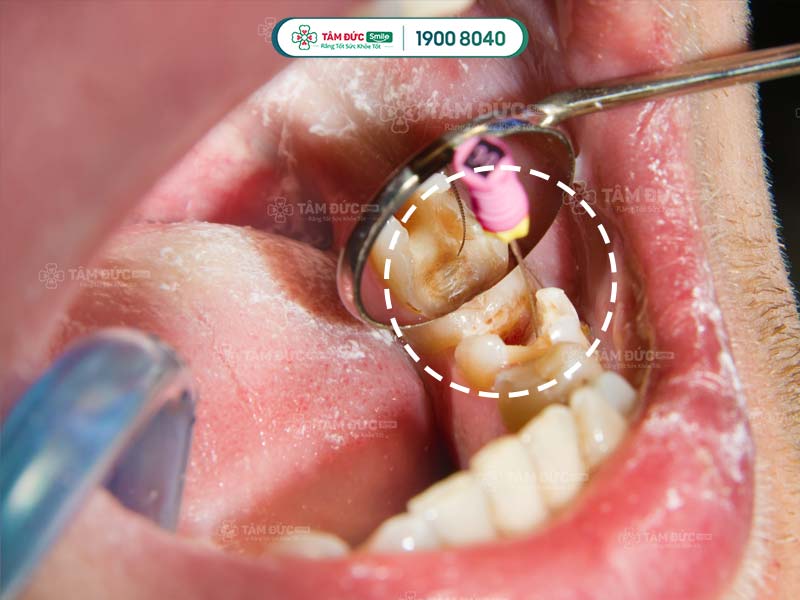

Lấy tuỷ răng lần 1 vẫn đau do còn sót ống tuỷ bị viêm

1.2. Do lấy sót ống tủy hoặc mô tủy

Trong quy trình điều trị tủy răng bị viêm nhiễm, nguyên tắc cơ bản nhất là làm sạch hoàn toàn mô tủy hư hại. Tuy nhiên, 1 số trường hợp do lấy sót ống tủy hoặc mô tủy nên làm cho lấy tủy răng lần 1 vẫn còn đau. Chủ yếu là do số lượng ống tủy quá nhiều hoặc do ống tủy có hình dạng phức tạp.

Mỗi chiếc răng khác nhau có số lượng ống tủy khác nhau. Ở nhóm răng cửa và răng nanh chỉ có 1 ống tủy, nên việc lấy tủy răng viêm tương đối dễ dàng. Riêng nhóm răng cối nhỏ và răng cối lớn có 2-3 ống tủy, thậm chí là 5 ống tủy. Cùng với hệ thống ống tủy phụ phức tạp và nhỏ, nên rất khó quan sát bằng mắt thường. Nếu bác sĩ điều trị không có kỹ năng tốt và kinh nghiệm dày dặn, sẽ rất dễ chữa sót tủy răng. Đây chính là nguyên nhân gây đau dai dẳng sau khi lấy tủy răng.

Hình dạng của tủy răng cũng rất phức tạp. Nếu ống tủy thẳng hoặc chỉ hơi cong nhẹ, thì quy trình lấy tủy rất suôn sẻ. Ngược lại, ống tủy bị cong nhiều hoặc thậm chí có dáng chữ S, dị dạng thì việc làm sạch mô tủy viêm rất khó thực hiện.

Để không lấy sót ống tủy hoặc mô tủy, bác sĩ thực hiện cần có kiến thức vững chắc về giải phẫu học. Ngoài ra, bác sĩ cần kiên nhẫn khi tìm kiếm tủy viêm, sử dụng thiết bị điều trị nội nha chuyên sâu. Đây là các yêu cầu cơ bản để xác định chính xác hệ thống các ống dẫn tủy, tạo điều kiện làm sạch hoàn toàn tủy răng viêm nhiễm.